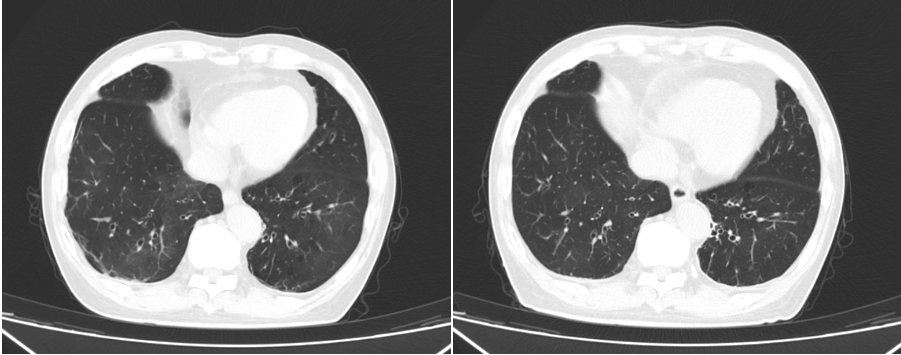

图2胸部CT(左2025-07-04,右2025-07-25)